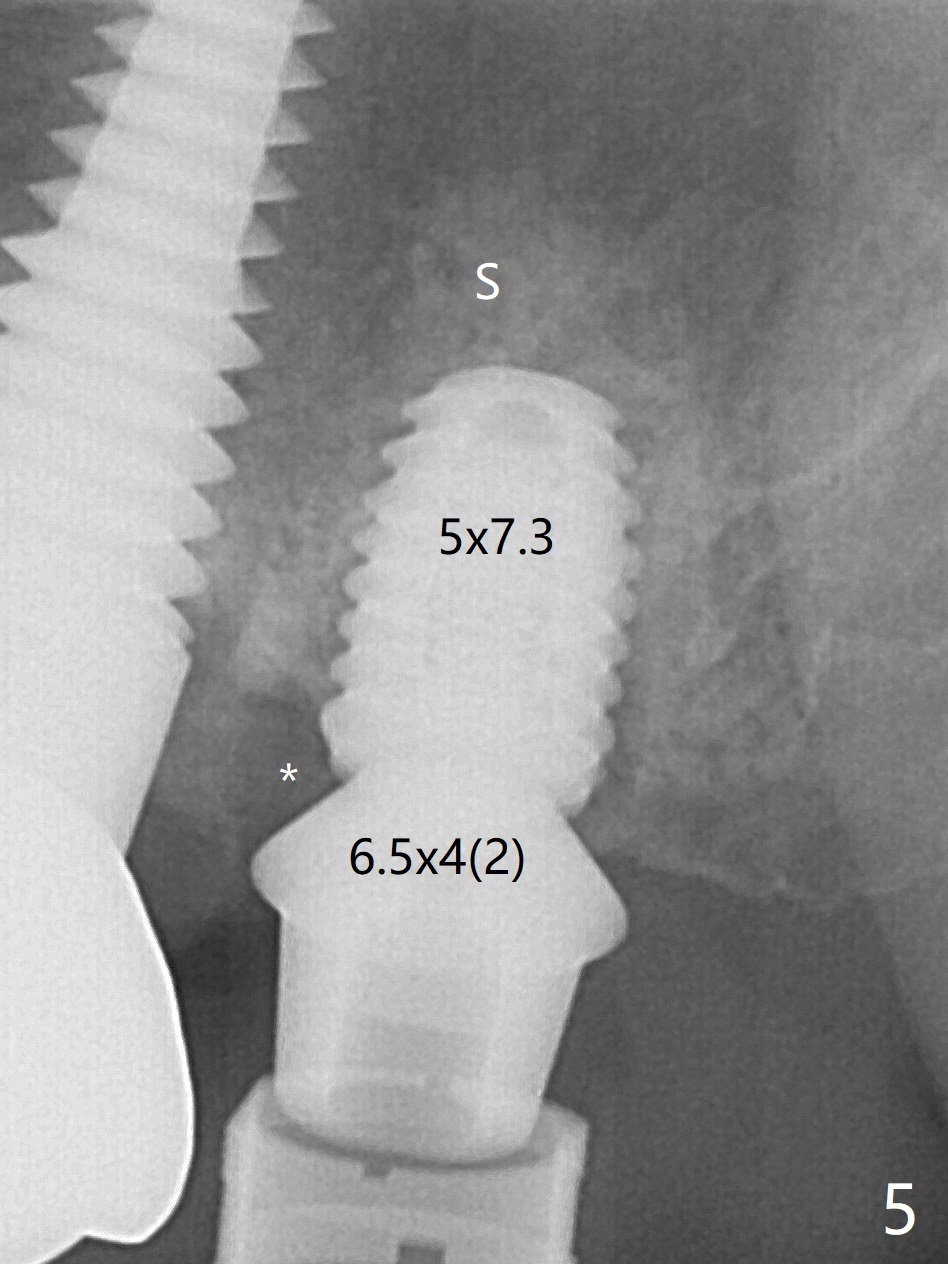

术前15号牙远中隐裂(图一:^),14号牙植体光滑面腭侧暴露(8年前腭侧窝植入),但是牙龈健康(图二)。14号牙牙槽窝没有肉芽组织,利用导板(Shinning Oral Scanner)完成3.5毫米钻洞,无法使用圆钻做内提升,改用4x10毫米报废植体提升,不幸窦膜好像破裂(因为薄),塞入半块PRF膜,促进修复,然后使用4.5x10毫米报废植体扩大植牙床(图三,四),无意达到部分提升(*),取出报废植体,发现植牙床没有穿孔了,加入少量粘性骨粉(图五:S(即使在窦内不容易分散))后,植入正式植体和基台。植体周围间隙(图五:*),使用刮匙,牙周探针,和长探针(图六)将骨粉输入深部(图七:*)。